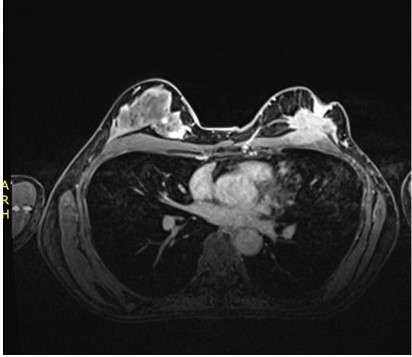

Se solicitó RMN de mama donde se evidenció una lesión sugerente de cáncer en región retro-areolar de la mama izquierda con infiltración del pectoral mayor. También, se evidenció signos sugestivos de involucramiento en la mama derecha (Figura 2). La RMN abdominal demostró múltiples lesiones en hígado sugerentes de metástasis. La gammagrafía ósea demostró una lesión focal en el húmero izquierdo y en el décimo arco costal derecho, sugerente de metástasis óseas.